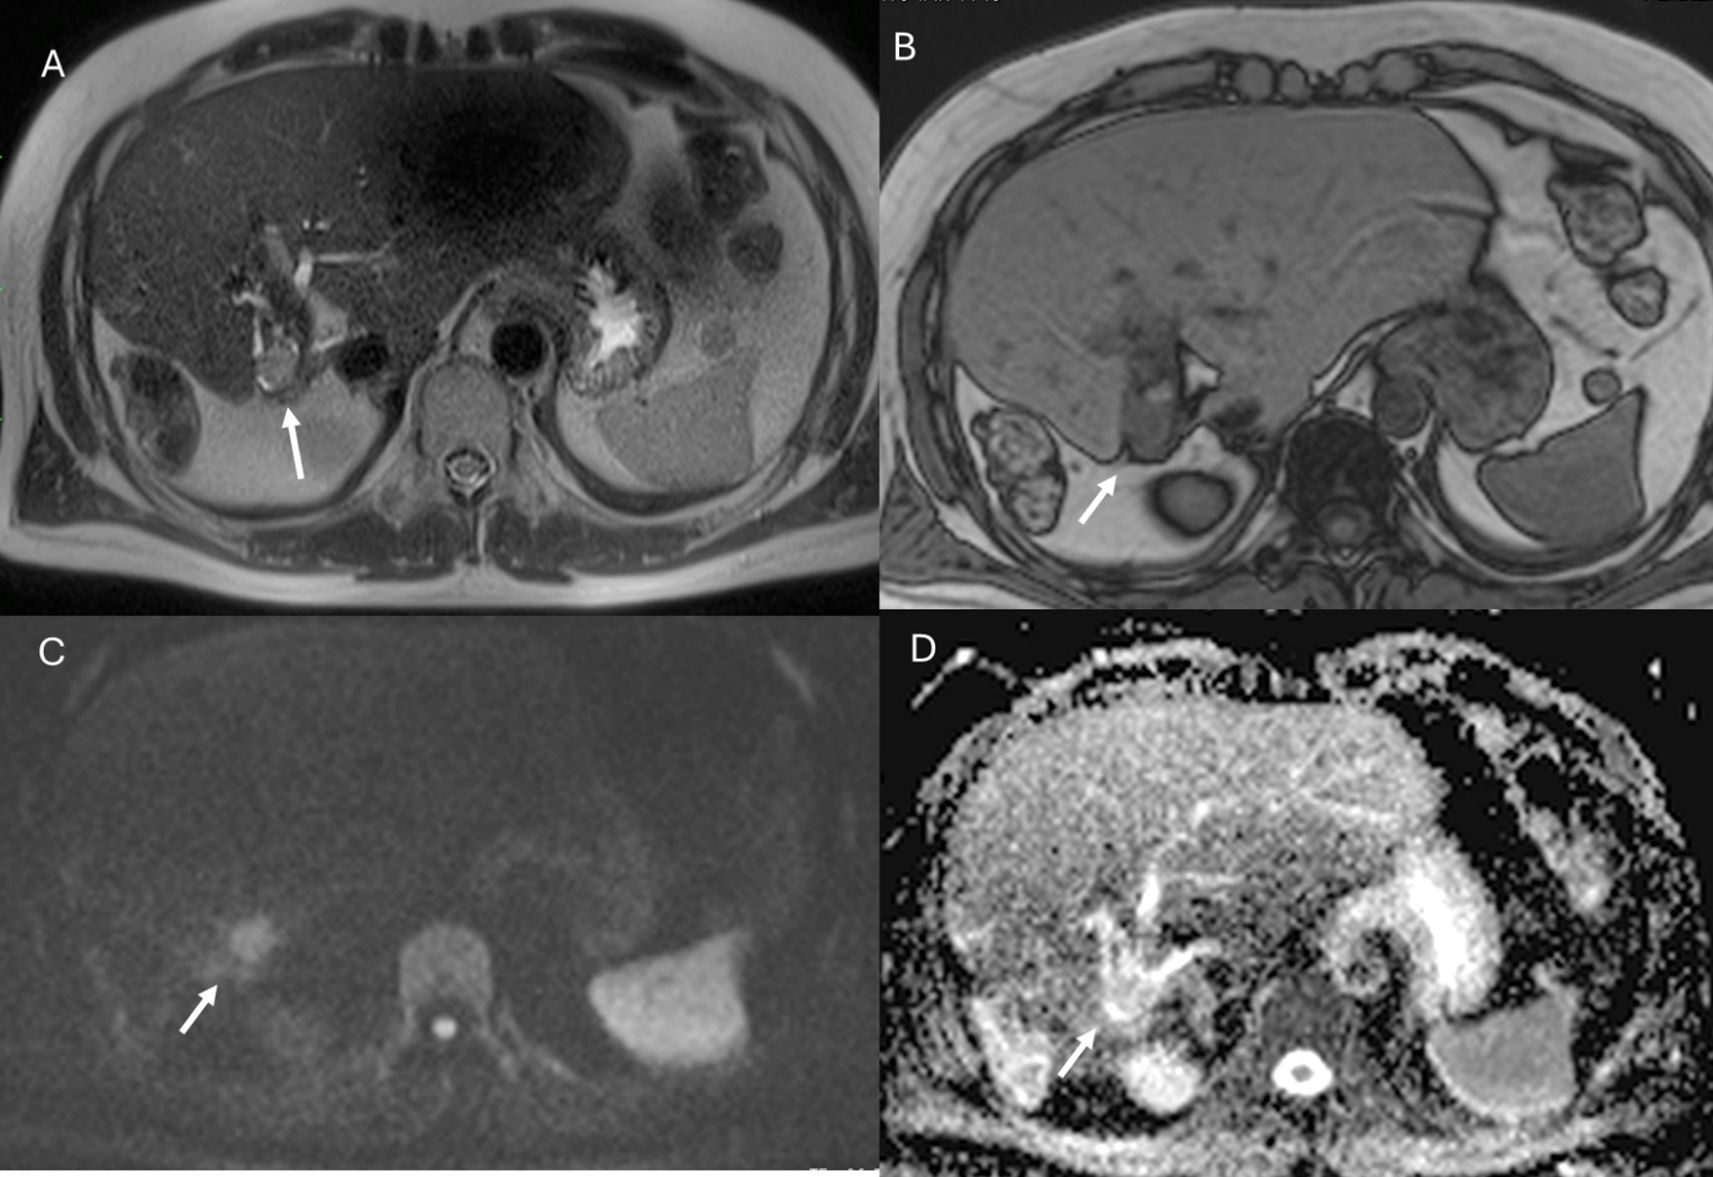

Figure 9. MRI of liver abscess after surgical resection. The lesion (arrows) shows hyperintense signal in T2-W sequence (A), hypointense signal in T1-W sequence (B), restricted diffusion on b = 800 s/mm² (C), and hypointense signal on ADC map (D). This demonstrates that a benign lesion can also show restricted signal and hypointensity on ADC maps.

Figure 10. MRI assessment of residual disease after surgical resection. The lesion shows similar features to the patient in Figure 9, with hyperintense signal in T2-W sequence (A), hypointense signal in T1-W out-of-phase sequence (B), restricted diffusion on b = 800 s/mm² (C), and hypointense signal on ADC map (D). In this case, DWI is suggestive of residual lesion.